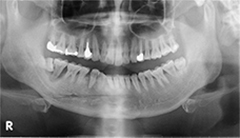

術前X線写真

術後X線写真